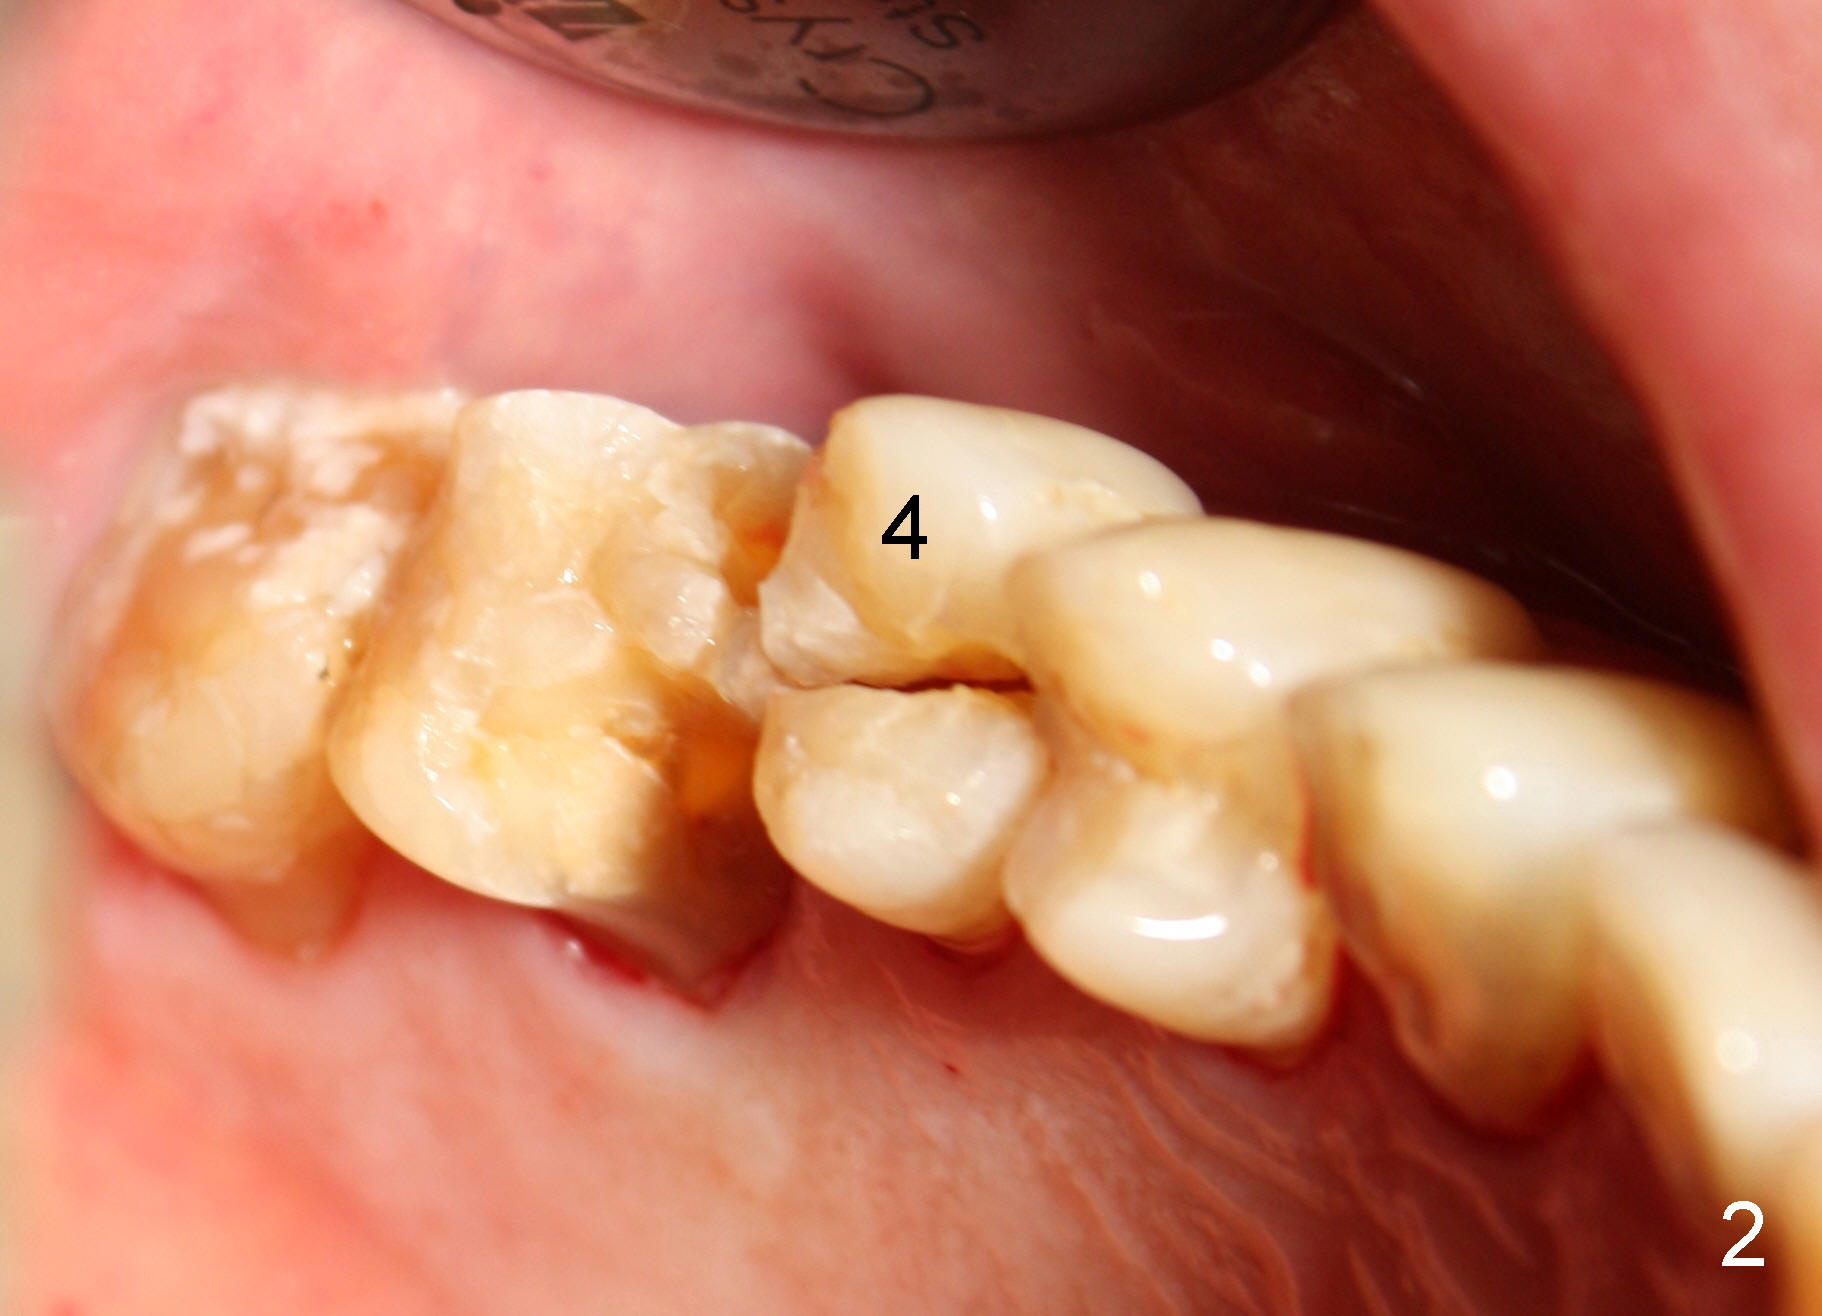

A 72-year-old man is a bruxer with #3 cusp fracture with chronic periapical radiolucency (Fig.1 *) and #4 acute crack.  It appears reasonable to take care of emergency (#4 extraction and immediate implant (Fig.3-7: 4.5x20 mm, 45 Ncm)) followed by root canal therapy or extraction for #3.  Eight (Fig.8) and 14 (Fig.9-11) days postop, the patient is doing fine and the wound heals normally.  But he does not agree any treatment for #3, since it is asymptomatic in spite of a fistula associated with the tooth (Fig.8,9 >).  Three months postop, the patient is still asymptomatic and is ready for #4 restoration since the tooth #28 cracks.  Follow-up PA shows the persistent distal gap (Fig.12 >, as compared to Fig.4), accompanied with crestal bone resorption (*).  Clinically the implant has mild mobility and light tenderness. The patient still refuses #3 treatment. It appears that the implant has failed to osteointegrate.  In brief, do not place an immediate implant next to active infection.